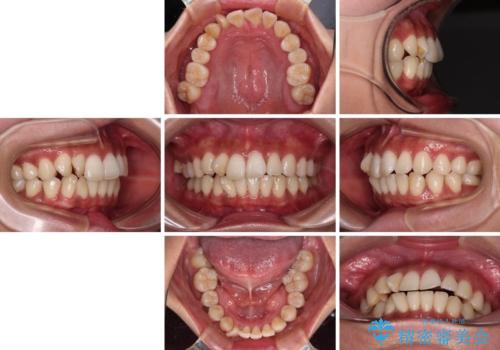

【モニター】上顎前突と奥歯の鋏状咬合 補助装置を用いたインビザライン矯正治療

- 前歯の歯列不正と奥歯の咬みにくさを気にして来院された患者様です。

インビザラインでの矯正治療を希望されていましたが、奥歯の咬み合わせがインビザライン単独では改善困難と判断されたので、補助装置を併用することとしました。

上顎最後臼歯は極端に外側を向いており、下顎骨に対して上顎骨が前方に位置していたため、補助装置により最後臼歯を一気に内側に引き込むとともに、上顎臼歯を後方移動させ、奥歯の咬み合わせが改善した後に、上下インビザラインにより歯列全体を整えていくこととしました。

奥歯の咬み合わせを事前に望ましい位置に改善したことで、インビザライン単独では改善が最も困難な状況を排除することができ、非常に理想的な仕上がりとなりました。